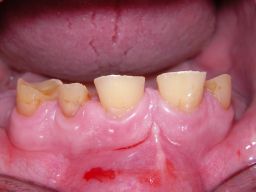

Das Hauptproblem dieses Falles lag im Oberkiefer - die über die Jahrzehnte abgeknirschten, kurzen Zähne erschweren Kronen, die durch eine Prothese belastet werden können. Die gewählte Lösung besteht darin, die Zähne nur rundherum zu beschleifen, aber nicht mehr zu kürzen und die Prothese mit einem Druckknopfsystem an die Zähne anzukoppeln, das ein "Spiel" aufweist, so daß die Prothese nicht als Hebelarm auf die schwachen Restzähne wirken kann. Rechts die beschliffenen Zähne kurz vorm Zementieren der Kronen.

Oberkieferrestzähne von vorne

Oberkieferrestzähne in Aufsicht

Oberkiefer vorm Zementieren